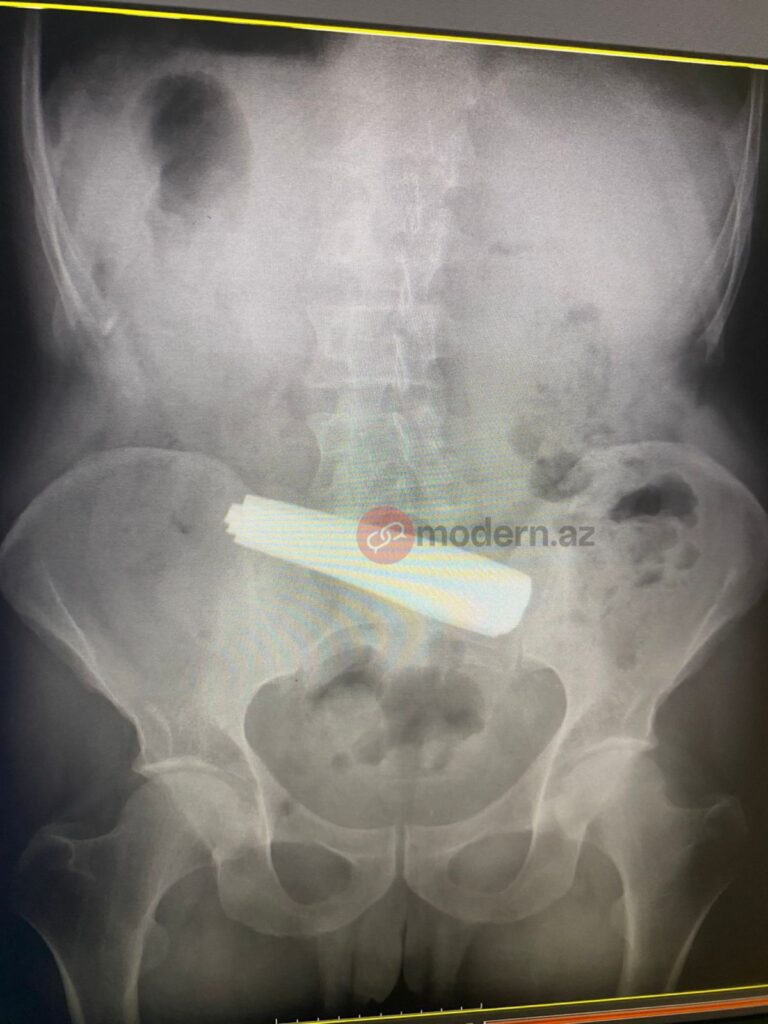

Bakıda bir nəfər 9 ədəd qaşıq udub.

Nəhayət, Bakı Sağlamlıq Mərkəzinə çatdırılan pasiyentə dərhal tibbi müdaxilə olunub. Məlumata görə, xəstə 9 ədəd metal qaşığı udub. Həkimlər tərəfindən həyata keçirilən əməliyyat uğurla başa çatıb.